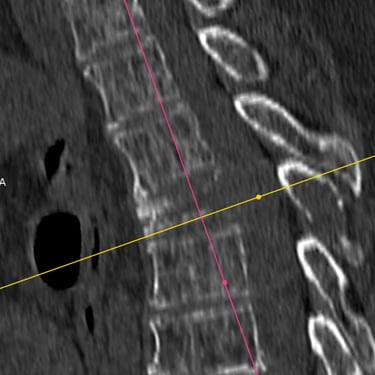

🧠 Fractura Vertebral Lumbar: Estabilización Segura con Fijación Transpedicular (FTP).

La fractura vertebral lumbar genera inestabilidad y dolor severo. La artrodesis con fijación transpedicular es una técnica quirúrgica eficaz que estabiliza la columna, previene desplazamientos vertebrales y mejora la recuperación funcional del paciente.